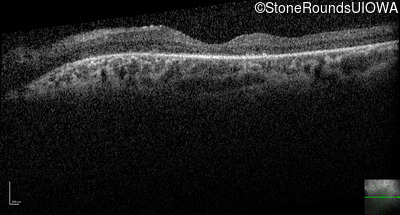

Optical Coherence Tomography - Left - 20/32

Exemplar / OCT Stack